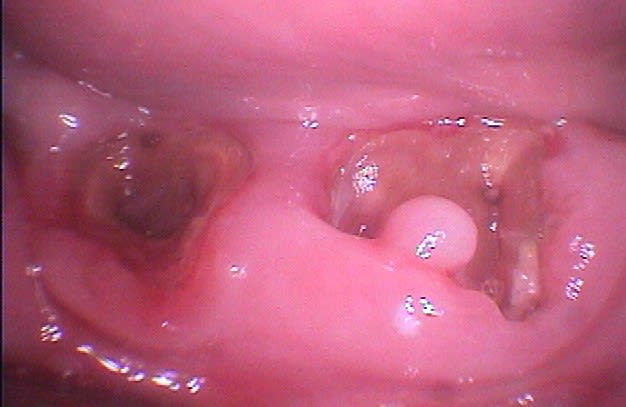

Cette même patiente, pimpante pour ses 90 ans et pleine de gaieté, viens me voir pour son nouvel appareil du bas qu'elle ne supporte pas. Avec surprise, je découvre dessous des chicots abandonnés par son ancien dentiste avec des inflammations gingivales. Radios prises, je lui propose de tenter de les récupérer pour lui réaliser des bridges en remplacement de son appareil, à l'inverse de ce qui se fait habituellement.

La racine résiduelle de la 37 était logée au fond d'un entonnoir gingival au ras de l'os et la 46 était trop délabrée pour la conserver entière. Après quelques séances de gingivoplasties et de tailles, le pari était gagné et les bridges ont pu être scellés, la patiente était radieuse!